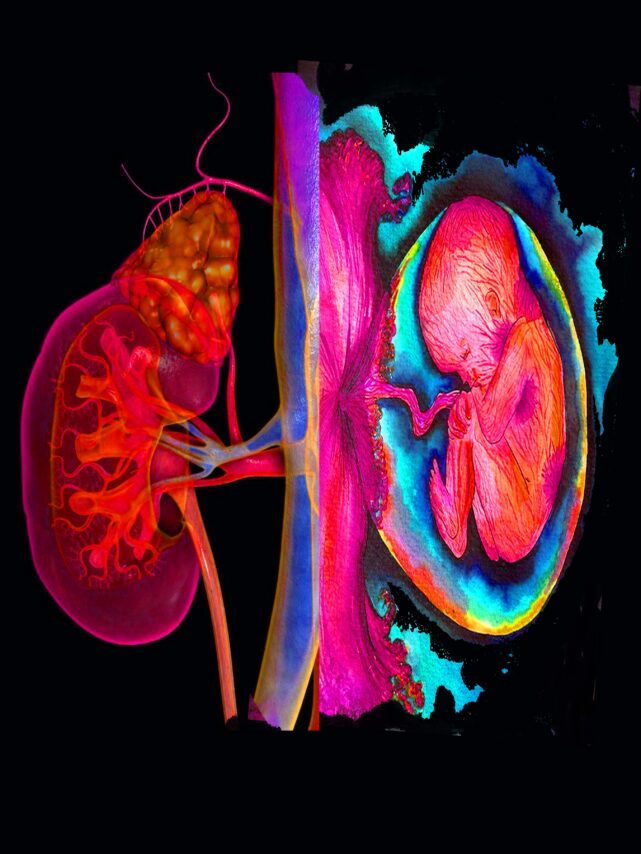

Author: Anil Kumar Saxena, Dubai

Digital art

Info:

The fetus nestled within the Renal outline radiates an ethereal glow, symbolizing hope born from adversity. It is a testament to the miracle of creation, where, even in the shadow of illness, the promise of renewal prevails. The swirling hues reflect the turbulence and warmth of this journey—a vivid gesture of survival, defying limits with grace. “Germination” embodies the profound triumph of life against the odds, where resilience blossoms within the most fragile vessel. (Inspired by the real-life experience when a young lady with ESRD due to lupus nephritis on dialysis delivered a healthy baby through C-section)

From:

Anil Kumar Saxena, Dubai